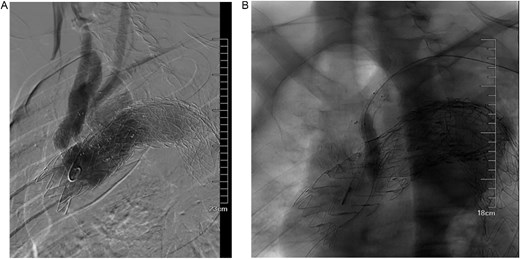

In November 2023, the patient had another recurrence of blood in the phlegm, and a CTA at an external hospital revealed extravasation around the thoracic aortic stent graft. And endoluminal embolization of the left bronchial artery was performed. Upon admission on December 1, 2023, symptoms had improved. It was hypothesized that the Gore aortic stent graft compressed the original subclavian artery BD stent graft, causing a type Ic endoleak (Fig. 7A). Left subclavian artery stent graft implantation and balloon dilation on December 4, 2023, improved the endoleak (Fig. 7B). However, the patient was readmitted on December 29, 2023, due to recurrent blood in phlegm, leading to transcatheter embolization of the right bronchial artery on January 3, 2024. Symptoms improved significantly, and the patient was discharged.

(A) It was hypothesized that the gore aortic stent graft compressed the original subclavian artery BD stent graft, causing a type Ic endoleak. (B) Left subclavian artery stent graft implantation and balloon dilation on December 4, 2023, improved the endoleak.